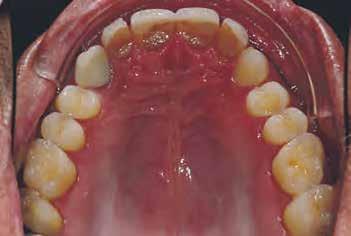

A cikkben egy fiatal nő kezelésének interdiszciplináris megközelítését foglaltuk össze, aki fogászati állapota miatt hoszszú ideje szenvedett fizikálisan és pszichésen is (1. ábra)

Amikor a 25 éves Andrea először konzultált a rendelővel, már több éve küszködött súlyos panaszokkal. Állapota két különböző betegségnek köszönhető, melyek egyrészt önmagukban, másrészt egymással kölcsönhatásban is súlyos következményekkel jártak. A fiatal nő veleszületett genetikai elváltozásban szenved, melynek tünete többek között a gyenge zománcfejlődés. Továbbá a beteget fibromyalgiával is diagnosztizálták, mely krónikus fájdalom rendellenesség, ami komoly tünetegyüttessel járó pszichés szorongás. A betegség egyik következménye az volt, hogy a páciens az elmúlt években átlagosan napi három-négyszer hányt. Az ebből fakadó savas erózió a már amúgy is veszélyben lévő fogazatot tovább roncsolta (2. ábra)

1. a–c ábrák: Kiindulási helyzet: fiatal páciens komoly fizikai és pszichés szenvedéssel.